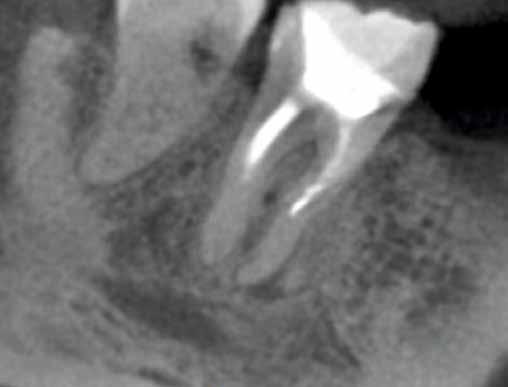

Egy 40 éves hölgy pácienst a jobb alsó második nagyőrlőfogának (47) panaszossága és kopogtatáskor jelentkező érzékenysége miatt irányították dr. Karaś rendelőjébe. A hagyományos technikával készített röntgenfelvételeken a beküldő orvos nem észlelt gyökércsatornák jelenlétére utaló jeleket, ezért úgy gondolta, hogy a fog endodonciai ellátása túlmutat saját kompetenciakörén.

Az első vizsgálat során CBCT-felvétel készült. A felvételen egy kis méretű radiolucens elváltozást észleltünk a mesialis gyökércsúcs körül. Ez alapján azt vélelmeztük, hogy elérhető lehet a mesialis gyökércsatornák átjárhatóságának biztosítása. A disztális gyökér körül nem láttunk gyulladásra utaló jeleket, így a panaszok hátterében valószínűleg a mesialis gyökér végén látható gyulladásos elváltozás állt. További leletként a mesio-bukkális gyökércsatornában (MB) egy törött lentulót is észleltünk (16. a–b ábra).

Az első kezelés célja a törött eszköz eltávolítása és a gyökércsatornák átjárhatóságának biztosítása volt. Helyi érzéstelenítés és a kofferdám felhelyezését követően a meglévő tömés eltávolításra került. Ezt követően láthatóvá vált, hogy mindhárom gyökércsatorna-bemeneti nyílást Endomethasone N fedi. Ezt az anyagot ultrahangos fej (U-file) és 5,25%os NaOCl alkalmazása révén távolítottuk el. Ezután a lentuló is láthatóvá vált. Sajnálatos módon a lentuló nem cementbe volt ágyazva, hanem a gyökércsatorna görbülete mögött egy fel nem tágított gyökércsatornafal-szakaszba ékelődött be. A tört részt kalcifikálódott szövetek borították. Ez alapján azt vélelmezzük, hogy az első kezelés során ezt a gyökércsatorna-szakaszt még élő fogbél töltötte ki. Ekkor azt a döntést hoztuk, hogy a kalcifikálódott szöveteket 10-15 percen keresztül végzett lézerrel aktivált folyamatos 5,25% NaOCl átöblítéssel megpróbáljuk eltávolítani. A terv sikeres volt, a

betört eszköz és a kalcifikálódott szövetek is eltávolításra kerültek. A betört műszer egészben történő eltávolításáról kontrollröntgen segítségével győződtünk meg (17. ábra)

A páciens öklendezése miatt a beavatkozások nehezen voltak elvégezhetőek. A kontrollröntgen elkészítése után a csatornát AutoSWEEPS módban alkalmazott SkyPulse lézerrel aktivált 17%-os EDTA és 5,25% NaOCl oldattal átöblítettük. A lézert néhány 15-20 másodperces ciklus idejére alkalmaztuk, majd a csatorna átjárhatóságát kézi tű segítségével ellenőriztük. Ekkor egy újabb kontrollröntgen készült, amely azt mutatta, hogy a tűnkkel az előzőleg elkészített gyökértömés végénél mélyebbre jutottunk (18. ábra). Ezután a fogat egy kompozitból készült ideiglenes töméssel zártuk, majd visszarendeltük egy következő időpontra.